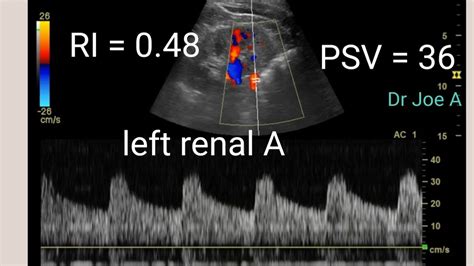

Renal Artery Doppler Ultrasound Normal Vs Abnormal Images Stenosis

Ultrasound (us) using a combination of grayscale, color, and spectral doppler. The normal transplanted kidney should demonstrate symmetric arterial and venous flow throughout the renal cortex on color doppler. Obtain the acceleration time (at) and acceleration index (ai) of the interlobar arteries in the upper pole, mid segment and lower pole.

Several waveforms may be needed to obtain an. It is useful for establishing a baseline examination for comparison at future. Proximal to the anastomosis, it is low resistance with persisting flow through diastole as this part of the artery. Doppler findings of low normal systolic velocities and parvus tardus waveforms in renal vessels with monophasic waveform in external iliac artery suggest arterial stenosis.